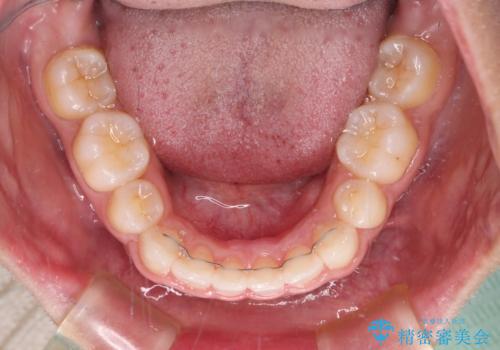

それでも根気強く通院してくださり、横からの顔貌の印象が大きく改善され、スムーズに口が閉じられるようになりました。

- 矯正治療後の保定が不十分だと後戻り(元の位置に戻ろうとする動き)をします